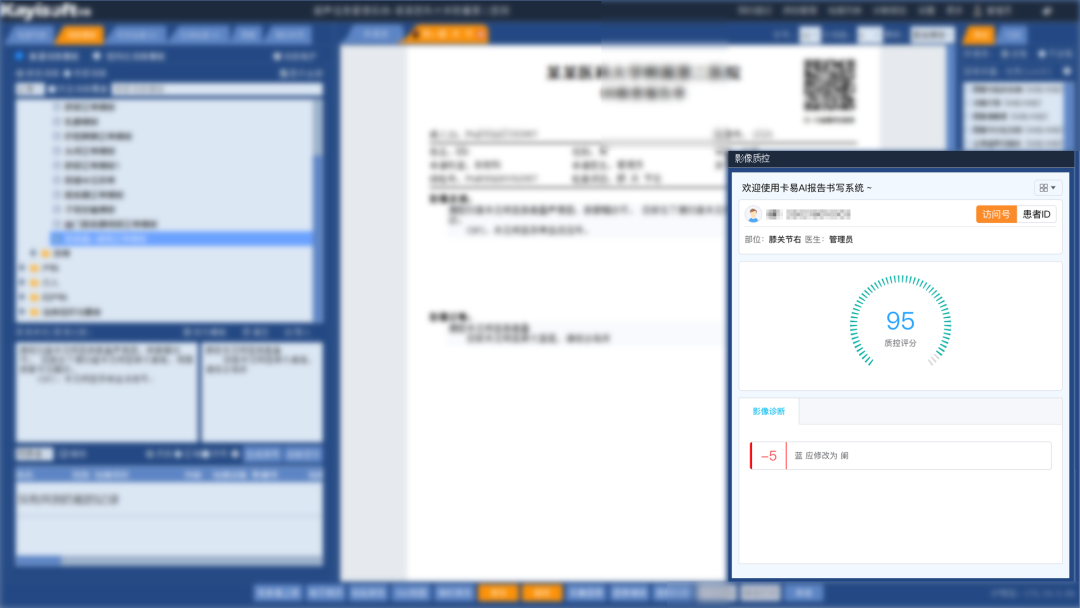

智能影像质控+报告质控

实时监控影像检查质量和报告质量,自动生成质控报告,确保影像数据的准确性和可靠性,从而提高医生诊断的准确性,帮助医疗机构提升管理水平。提供海量影像数据和AI分析工具,助力医疗机构开展临床科研和学术研究。